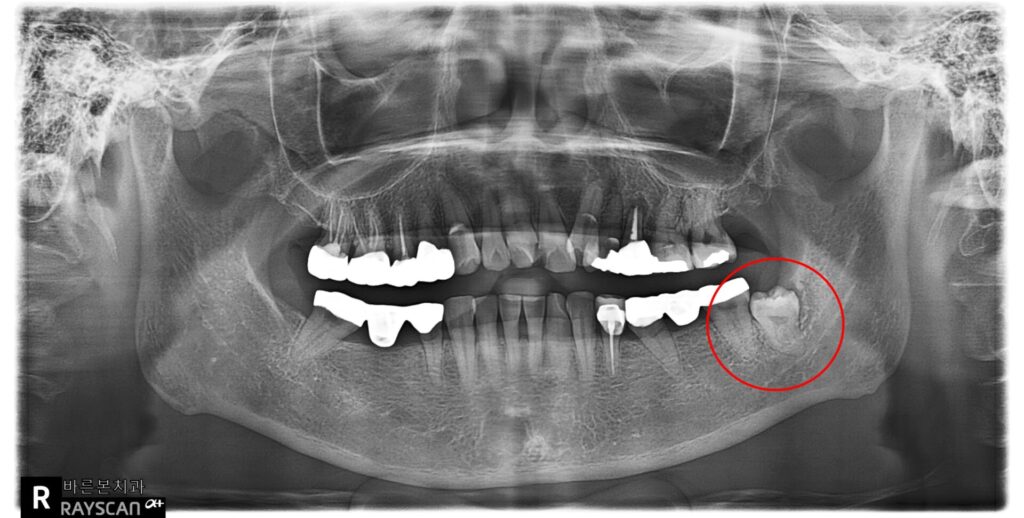

X-ray 사진입니다.

왼쪽 아래 매복사랑니가 보이고

(빨강색동그라미)

사랑니머리가 금으로 씌워진 어금니를

약간 밀고 있는 듯한 모습입니다.